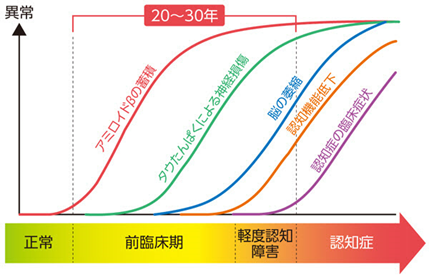

■ 認知症の背後で起こっている“ゆっくりした変化”

認知症は突然始まるわけではありません。

実際には、症状が出るよりもはるか前から、脳の中で小さな変化が積み重なっています。

■ アミロイドβとは? —— 発症の20〜30年前から蓄積が始まる

重要なのは次のポイントです。

アミロイドβの蓄積は、症状が出る20〜30年前から始まる。

これは世界的に確立されつつある理解で、

“認知症は発症の前から長い時間をかけて準備されていく病気”ということを意味します。

症状が出るころには、すでに脳の中で相当量の蓄積が進んでいることが多く、

早期予防が大切とされる根拠にもなっています。

■ “原因物質の蓄積”と“症状”の間には長い時間の差がある

研究の進展により、多くの専門家は次のように理解しています。

アミロイドβの蓄積は「始まり」

・タウの異常が「進行」

・神経細胞の障害が「症状」

ここで重要なのは、

症状は“最後にあらわれる現象”である

ということです。

症状がない段階でも、

脳の中ではすでに長い時間をかけて変化が進んでいる可能性があります。

だからこそ、

症状が出てから慌てて対応するのではなく、

症状が出る前の生活習慣や早期の受診・検査が大切になります。